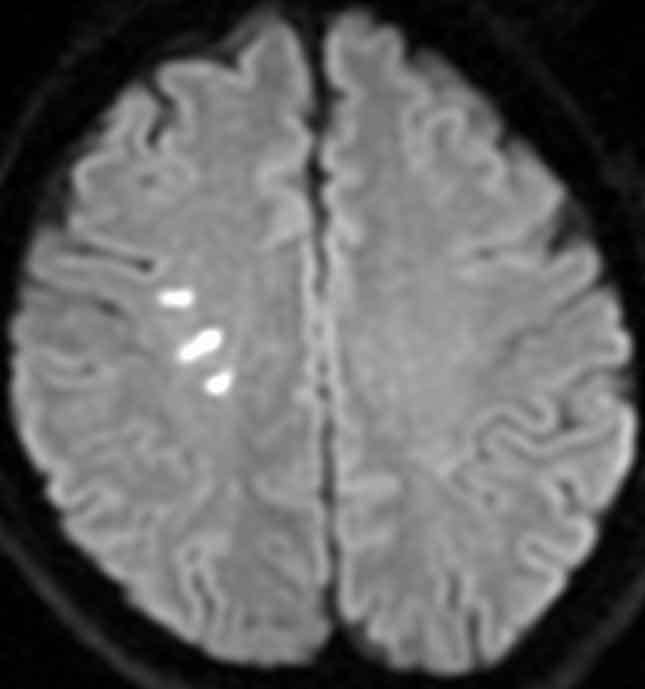

頭部MRA検査で脳の血管を撮影しました。

![]()

後大脳動脈という後頭部の血管が所々細くなっており(数珠状変化)、RCVSと診断しました。